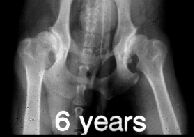

RTG snímek se provádí v tzv. extenzní ventrodorzální

projekci. Znamená to, že se psí pacient rentgenuje ve hřbetní poloze s

nataženými pánevními končetinami navzájem rovnoběžně dozadu. K

dokonalému napolohování psa se používá zvláštní lůžko ve tvaru písmene

"V" na průřezu.

Pro objektivní posouzení DKK by měl být snímek

symetrický, jelikož špatně zhotovený snímek může vést k chybné

interpretaci nálezu. Na snímku by tedy měla být zachycena celá pánev,

kost křížová a obě stehenní kosti včetně kolenních kloubů, pouze u

velkých a obřích plemen je dovoleno posunout pánev tak, že na snímku

nejsou vidět obě pately (čéšky). Stehenní kosti by měly probíhat

rovnoběžně mezi sebou a součastně s podélnou osou těla.

ŠPATNĚ PROVEDENÝ RTG SNÍMEK!!

Projekce není symetrická - stehenní kosti a podélná

osa těla nejsou rovnoběžné. |

Dále by se měla věnovat velká pozornost projekčně

dokonalému snímku. Jakékoli nevyhovující kvalita snímku může poté opět

negativně ovlivnit konečné hodnocení snímku, zejména v případě

hraničních stupňů dysplazie.

Na levém snímku můžeme vidět kyčelní klouby zdravého

zvířete, ale na druhém snímku je zrentgenované zvíře postižené těžkou

dysplazií.